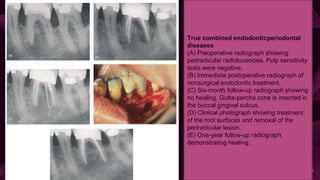

True combined endodonticperiodontal

diseases

(A) Preoperative radiograph showing

periradicular radiolucencies. Pulp sensitivity

tests were negative.

(B) Immediate postoperative radiograph of

nonsurgical endodontic treatment.

(C) Six-month follow-up radiograph showing

no healing. Gutta-percha cone is inserted in

the buccal gingival sulcus.

(D) Clinical photograph showing treatment

of the root surfaces and removal of the

periradicular lesion.

(E) One-year follow-up radiograph

demonstrating healing.